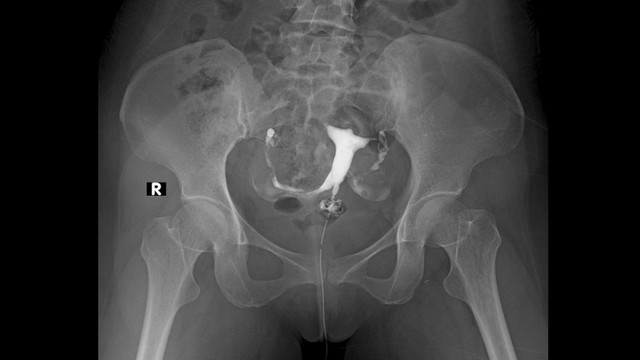

U xơ tử cung là bệnh lý phổ biến ở phụ nữ trong độ tuổi sinh sản, ảnh hưởng đến chất lượng cuộc sống và khả năng sinh sản. Trong những năm gần đây, phương pháp điều trị u xơ tử cung bằng sóng siêu âm hội tụ cường độ cao (HIFU) đã nổi lên như một lựa chọn không xâm lấn, hiệu quả và an toàn, đặc biệt phù hợp với những phụ nữ mong muốn bảo tồn tử cung.